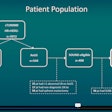

Many young women with breast cancer symptoms delay care

April 12, 2024